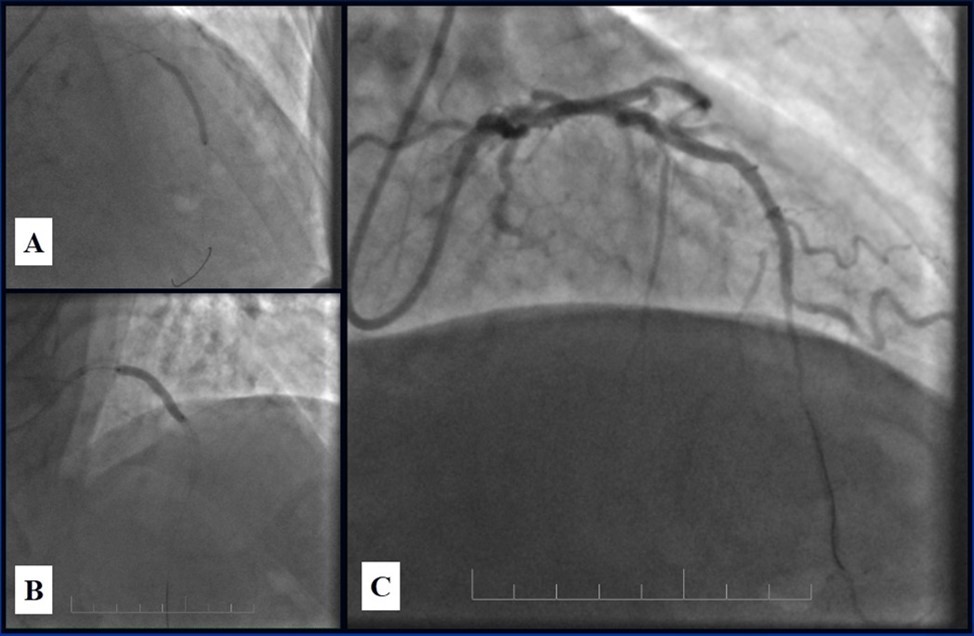

In the first stage, despite the fact that BMS is contraindicated in diabetic patients, RCA was stented with 3 bare-metal stents (BMS) (Rebel, Boston Scientific) (due to financial problems - drug-eluting stents was not covered by insurance). We used BMS to have at least temporarily patent RCA during LMCA stenting (Figure 5) (we believe that, when RCA is functional, LMCA stenting is safer). LAD was stented with 2 drug-eluting stents (Resolute Integrity, Medtronic). After the first PCI patient’s symptoms were relieved (Figure 6).

Figure 6.A, B - Stenting of the LAD with DES; C - Angiography result.

Figure 7.Patent stents in LAD; A – AP-cranial 30° projection, B – Right anterior oblique 20°/caudal 20° projection.